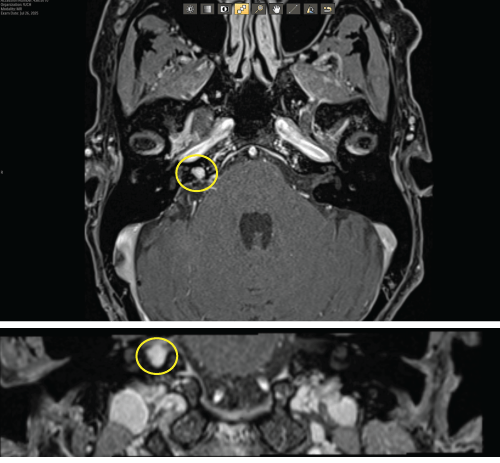

Hello friends. I haven’t posted in a while, but my (and Ella’s – now “Ace”) journey is not over, unfortunately. I had an MRI in July and it is showing some regrowth. It is small – like the size of a pea, but I need to address it. You can see it in these scans. That little white dot on the left side of the image is the regrowth. It’s definitely different than the other side. They are recommending a procedure called gamma knife.

Here is a description of what gamma knife is: This approach may be used if the acoustic neuroma is growing, with the goal of preventing further tumor growth. With stereotactic radiosurgery, a highly precise single dose of radiation is delivered to the tumor. The procedure’s success rate at stopping tumor growth is usually greater than 90%. It may increase the amount of hearing loss in the affected ear, but risk of creating new symptoms like facial weakness should be low.